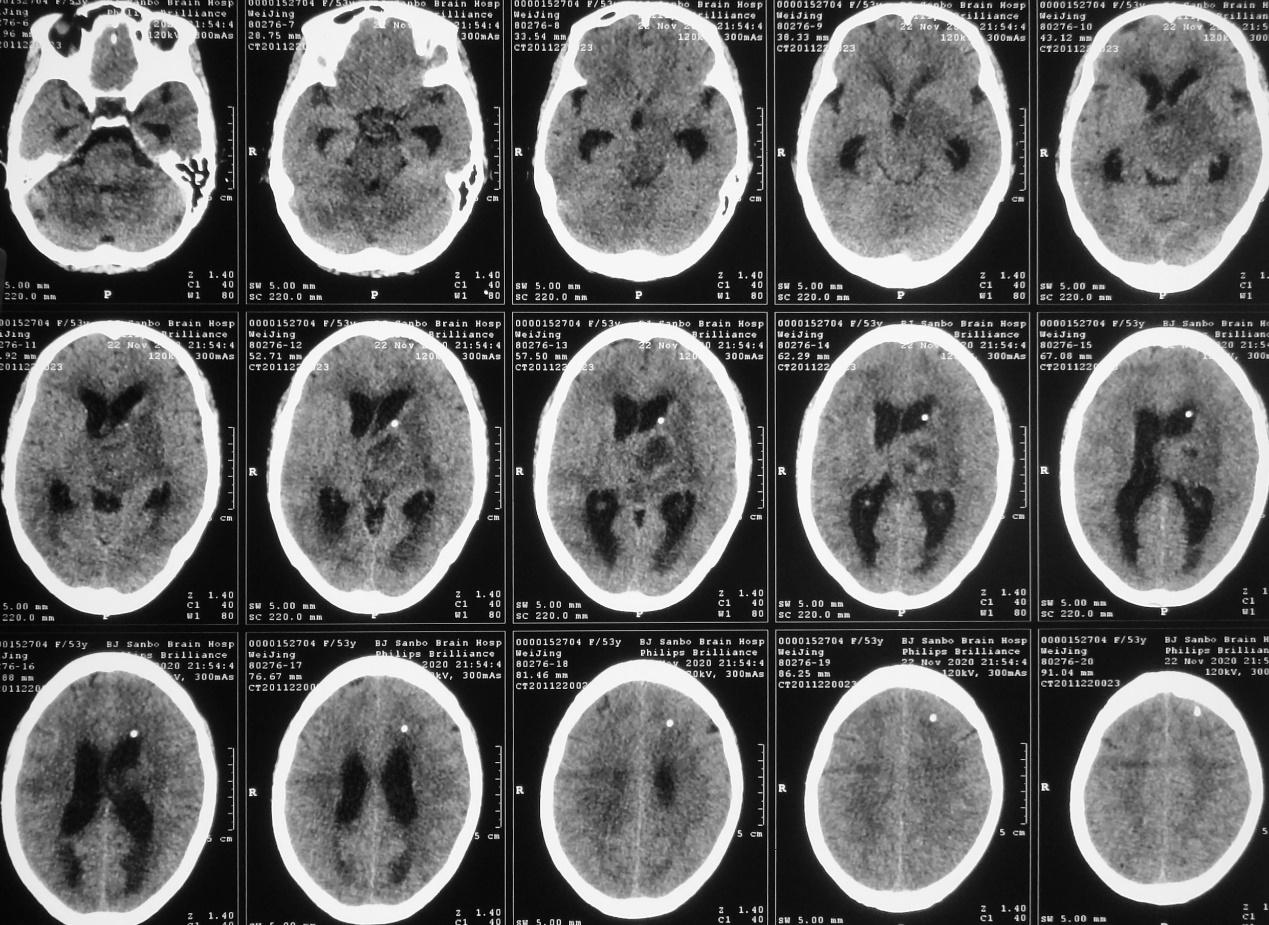

脑室外引流术后第2天即2020年11月22日早上8点,患者好转为清醒,复查头颅CT见左侧脑室缩小( 图-4 );但患者出现发热,引流出的脑脊液浑浊,医生考虑患者丘脑病变为脑脓肿,给予头孢曲松抗炎治疗。

图-4: 2020年11月22日头CT

但当天晚上21:00,意识再次变差为嗜睡,复查头颅CT见脑室扩张( 图-5 ),考虑脑室引流不通畅,给予调整引流管后引流好转。

图-5: 2020年11月22日晚上头CT